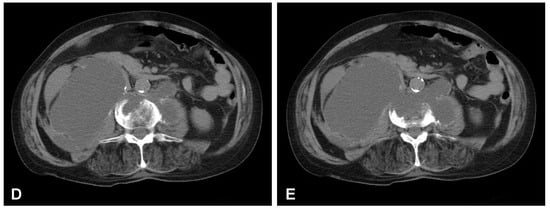

A 59-year-old man presented to the hospital with atypical abdominal pain for a few days, three weeks after sustaining a low-energy fall. At the time of admission, the patient had normal upper and lower extremity strength and no pathologic reflexes, as well as no bowel or bladder incontinence. The initial performed plain radiograph of the abdomen demonstrated a fracture line completely slicing through the L3/L4 intervertebral disc space and features of ASH (Figure 1). The additional performed computed tomography (CT) scans demonstrated a three-column fracture of L4 vertebrae with a suspicious transdiscal injury at the L3/L4 level, which was morphologically classified as type B3/C according to the Arbeitsgemeinschaft für Osteosynthesefragen (AO) spine classification. Moreover, at the fracture level, the hypodense area communicating intervertebral disc space with both psoas major muscles forming a massive, well-defined fluid-like collection in the right retroperitoneum was observed (Figure 2). In addition, contrast-enhanced CT (CE-CT) showed a thick enhancing wall and internal septae within an area measuring a total of 10 cm × 20 cm × 10 cm (TR × AP × CC) (Figure 3). Furthermore, the performed magnetic resonance imaging (MRI) scans confirmed the cystic nature of the lesion, which had no specific characteristics and demonstrated intensities that were similar to those of cerebrospinal fluid (CSF) (Figure 4). Taking into consideration the history and radiological features, suspicion of spondylodiscitis with osteomyelitis features and retroperitoneal abscess formation was provided by the radiologist. Blood analysis performed on admission revealed the following results: hemoglobin (Hb): 9.6 g/dL; platelet (PLT): 192 × 109/L; white blood cell (WBC): 9.7 × 109/L; and creatinine (CREA): 0.42 mg/dL. Despite the lack of infection symptoms, the patient was empirically administered intravenous antibiotics, including meropenem (1 g every 8 h) and vanomycin (1 g every 12 h), without waiting for microbiological confirmation.

Figure 3. Preoperative sagittal (A), coronal (B), and axial (C,D) CT scans (contrast enhanced) of the lumbar spine demonstrating hypodense area with enhancing wall at the L3/L4 intervertebral disc space communicating with both psoas major muscles forming massive well-defined fluid-like collection in the right retroperitoneum.